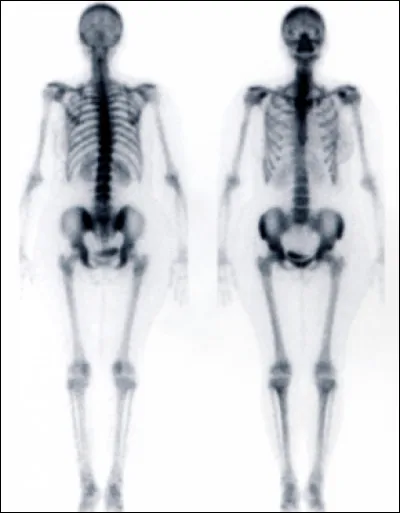

On termine ce quiz avec la scintigraphie. Pas de rayons X ou de champ magnétique, ici on utilise la radioactivité : on donne au patient un composé radioactif spécifique qui va par exemple se fixer sur le squelette. On va alors avoir un reflet du métabolisme osseux qui sera augmenté entre autres en cas d'infection ou de processus tumoral. Dans quel service utilise-t-on cette technique ?